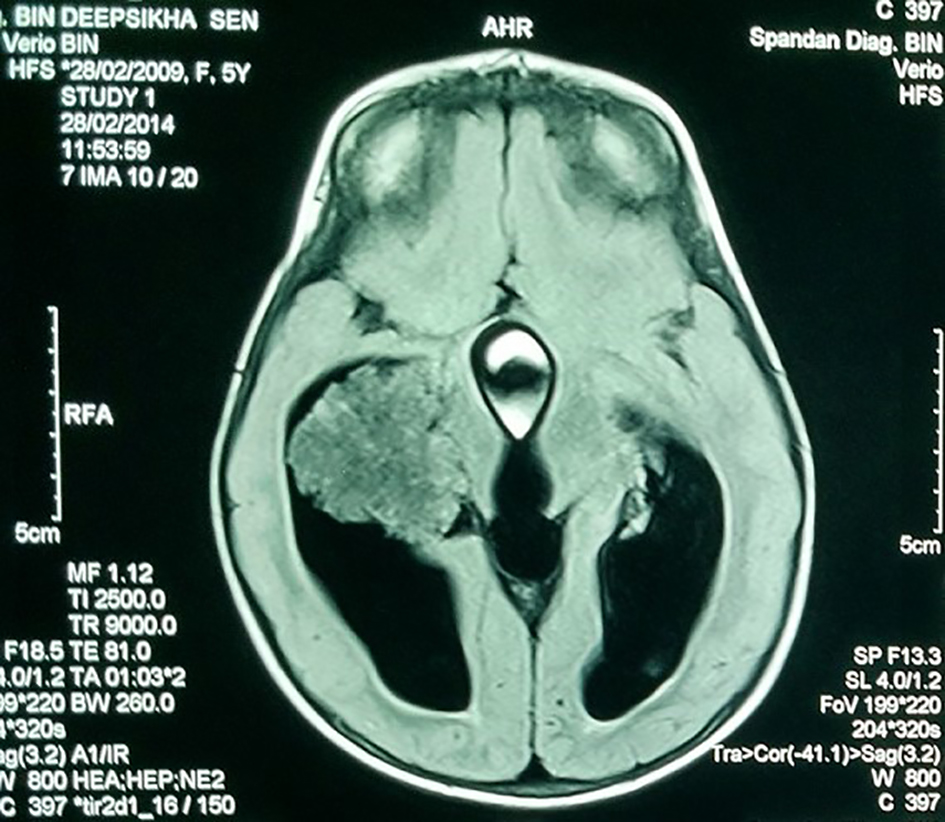

A 7-year-old girl presented with progressive head enlargement since birth, features of raised intracranial pressure in the form of headache, vomiting, excessive crying and excessive drowsiness. Her visual acuity was reduced due to secondary optic atrophy. She had no history of any seizures since birth. Magnetic resonance imaging (MRI) revealed a large hypointense lobulated mass (T2 and FLAIR) originating from the choroid plexus in the temporal horn of the right lateral ventricle measuring almost 50 × 45 × 40 mm in size. All supratentorial ventricles were dilated and the mass was causing compression over adjoining midbrain (Figs. 1-3). With a provisional diagnosis of a choroid plexus mass, the patient was taken up for surgery. A ventriculo-peritoneal shunt was placed for the drainage of excessively forming CSF 2 days prior to the surgery. A right temporal craniotomy was performed and the temporal horn was opened through mid temporal sulcus and the mass was reached. It was a firm friable and vascular mass arising from the choroid plexus on the temporal horn. The tumor had its vascular supply from the anterior choroidal artery.

![]() Click for large image | Figure 2. MRI showing the hypointense lobulated mass in the lateral ventricle. |